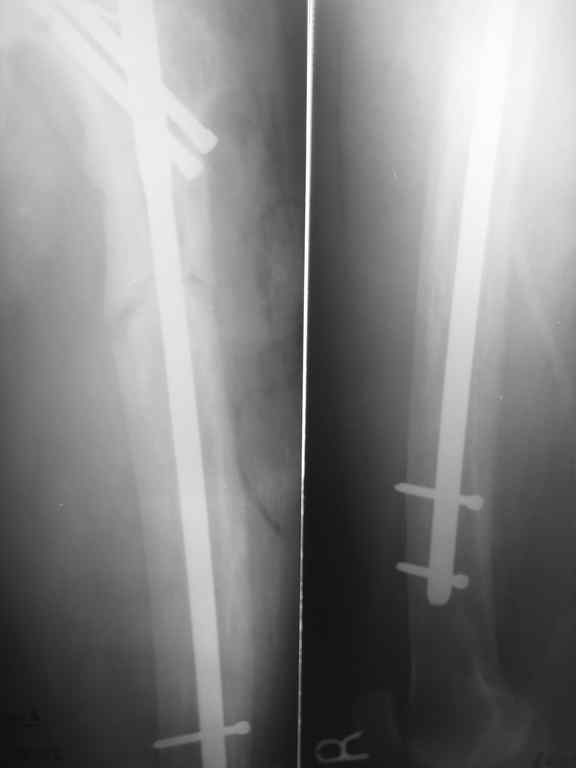

Пациент 82 лет, поступил через 5 мес. с несросшимся переломом после открытого интрамедуллярного остеосинтеза. Выполнили реостеосинтез стержнем 12 мм. ( мах. доступного нам в 2003 г.) Через 4 мес динамизация. В течении 2х лет сращения нет, тем не менее конечность опорна (ходит с тростью). От очередного реостеосинтеза отказались из-за сопутств. патологии.

Еще один пример. Пациентка с юга России, прислала рентгенограммы через год. На сегодня прошло 2 г. 8 мес. после операции. Несмотря на не очень убедительный процесс сращения, пациентка ходит. Учитывая остеопороз при Педжете, решили, что динамизировать вообще не нужно.